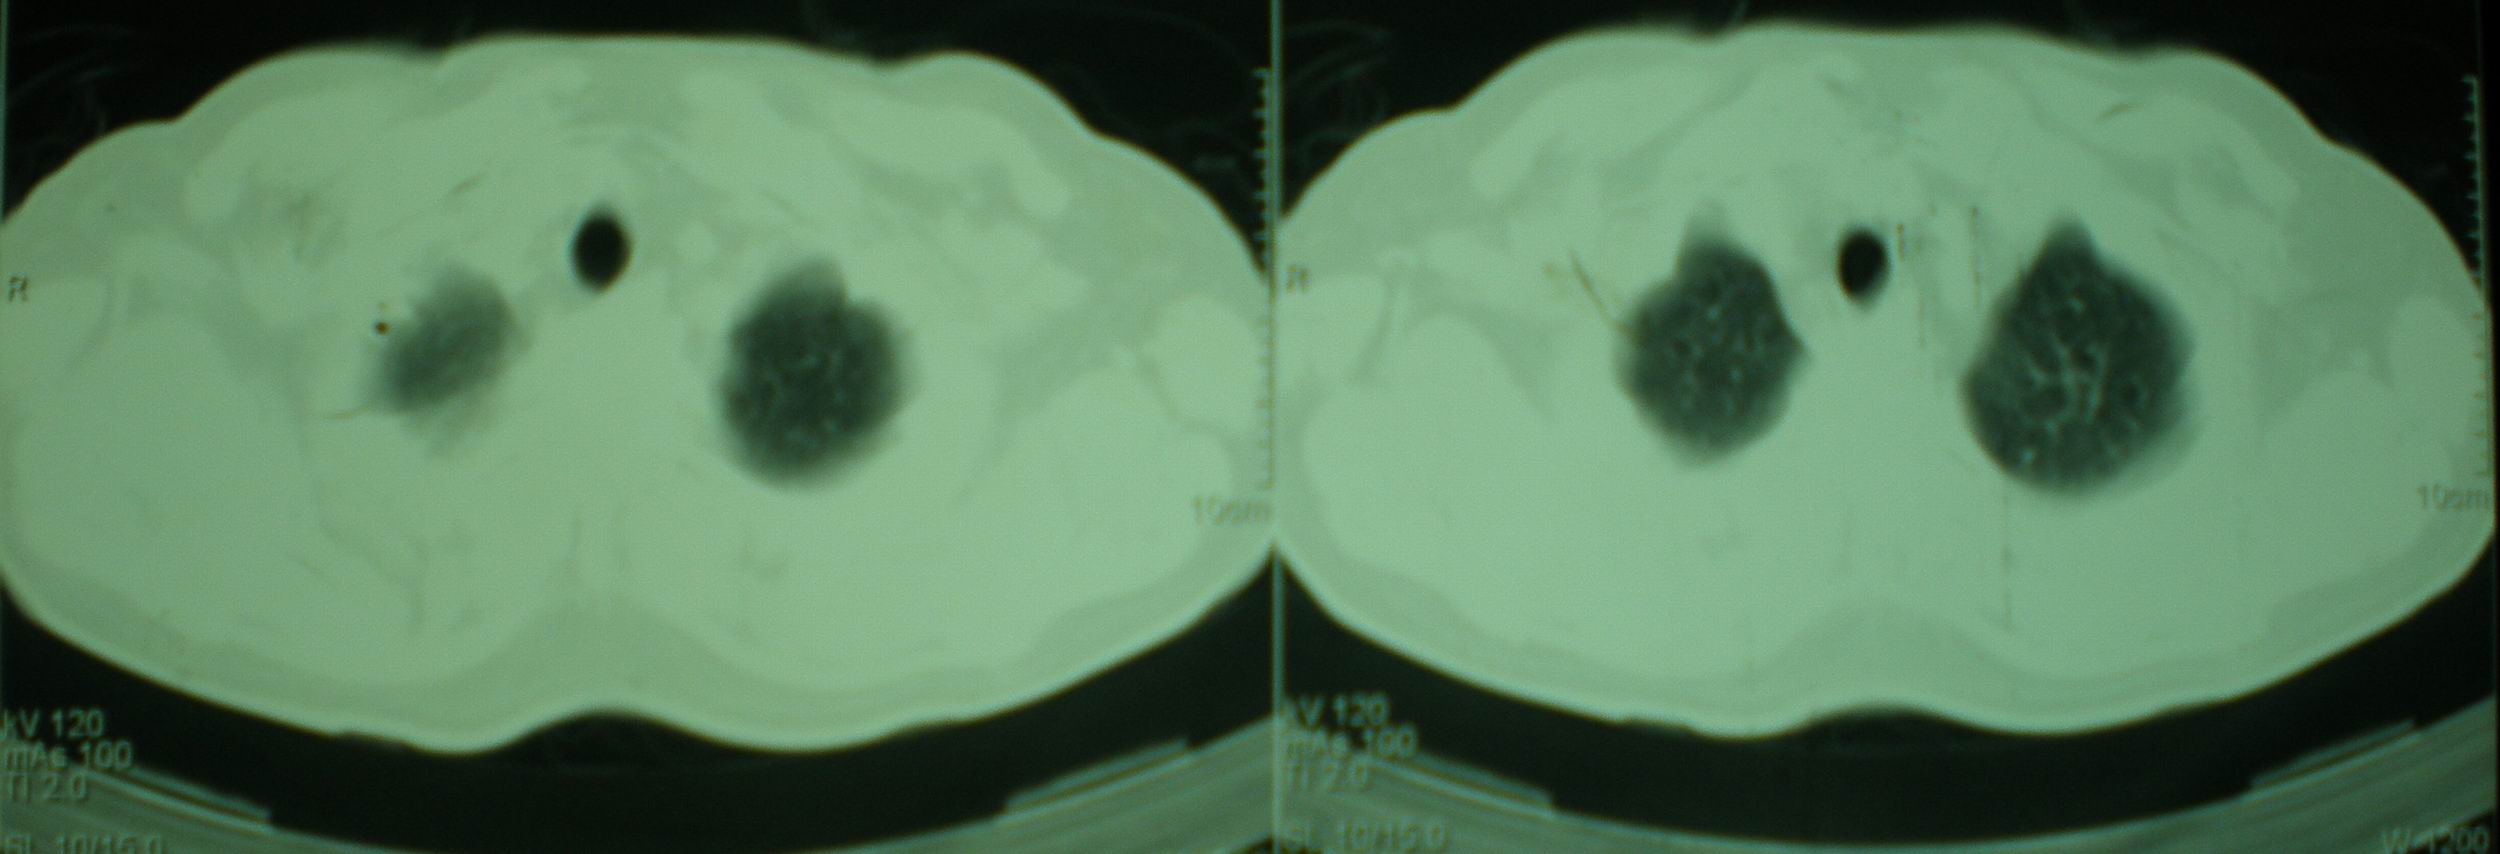

标题: CT16695:男,52岁,复查,有两次对比片及上级医院住院小结 [打印本页]

标题: CT16695:男,52岁,复查,有两次对比片及上级医院住院小结

病人资料:男,52岁,因体癣股癣等皮肤病行激素治疗,因突然大剂量减药而起病,病情危急,9月8日曾在上级医院住院治疗,9月18日复查了ct片,相关检查及住院小结以图片资料上传。

2008年11月18日今天的ct片